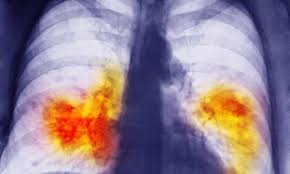

Exacerbating physical inactivity The direct meaning of a fatal disease like cancer in a person's body is the uncontrolled growth of cells in an organ or place. The uncontrolled growth of cells affects the tissues of the body and in most cases engulfs the rest of the body. From a one-year-old infant to an elderly 80-90 years old, there can be such unnecessary growth of cells that causes more than a hundred types of cancer. Some of the common types of cancer are breast cancer, cervical cancer, blood cancer, bone cancer, pancreatic cancer, prostate cancer, kidney cancer, lung cancer, mouth and throat cancer, skin cancer and brain cancer etc.

Cancer is often caused due to lack of physical activity, harmful and contaminated food, consumption of drugs like alcohol and tobacco etc. Apart from this, obesity is one of the major causes of cancer. cancer has also been transferred from one generation to another due to genetic reasons. Sometimes the side effects of medicines lead to cancer.